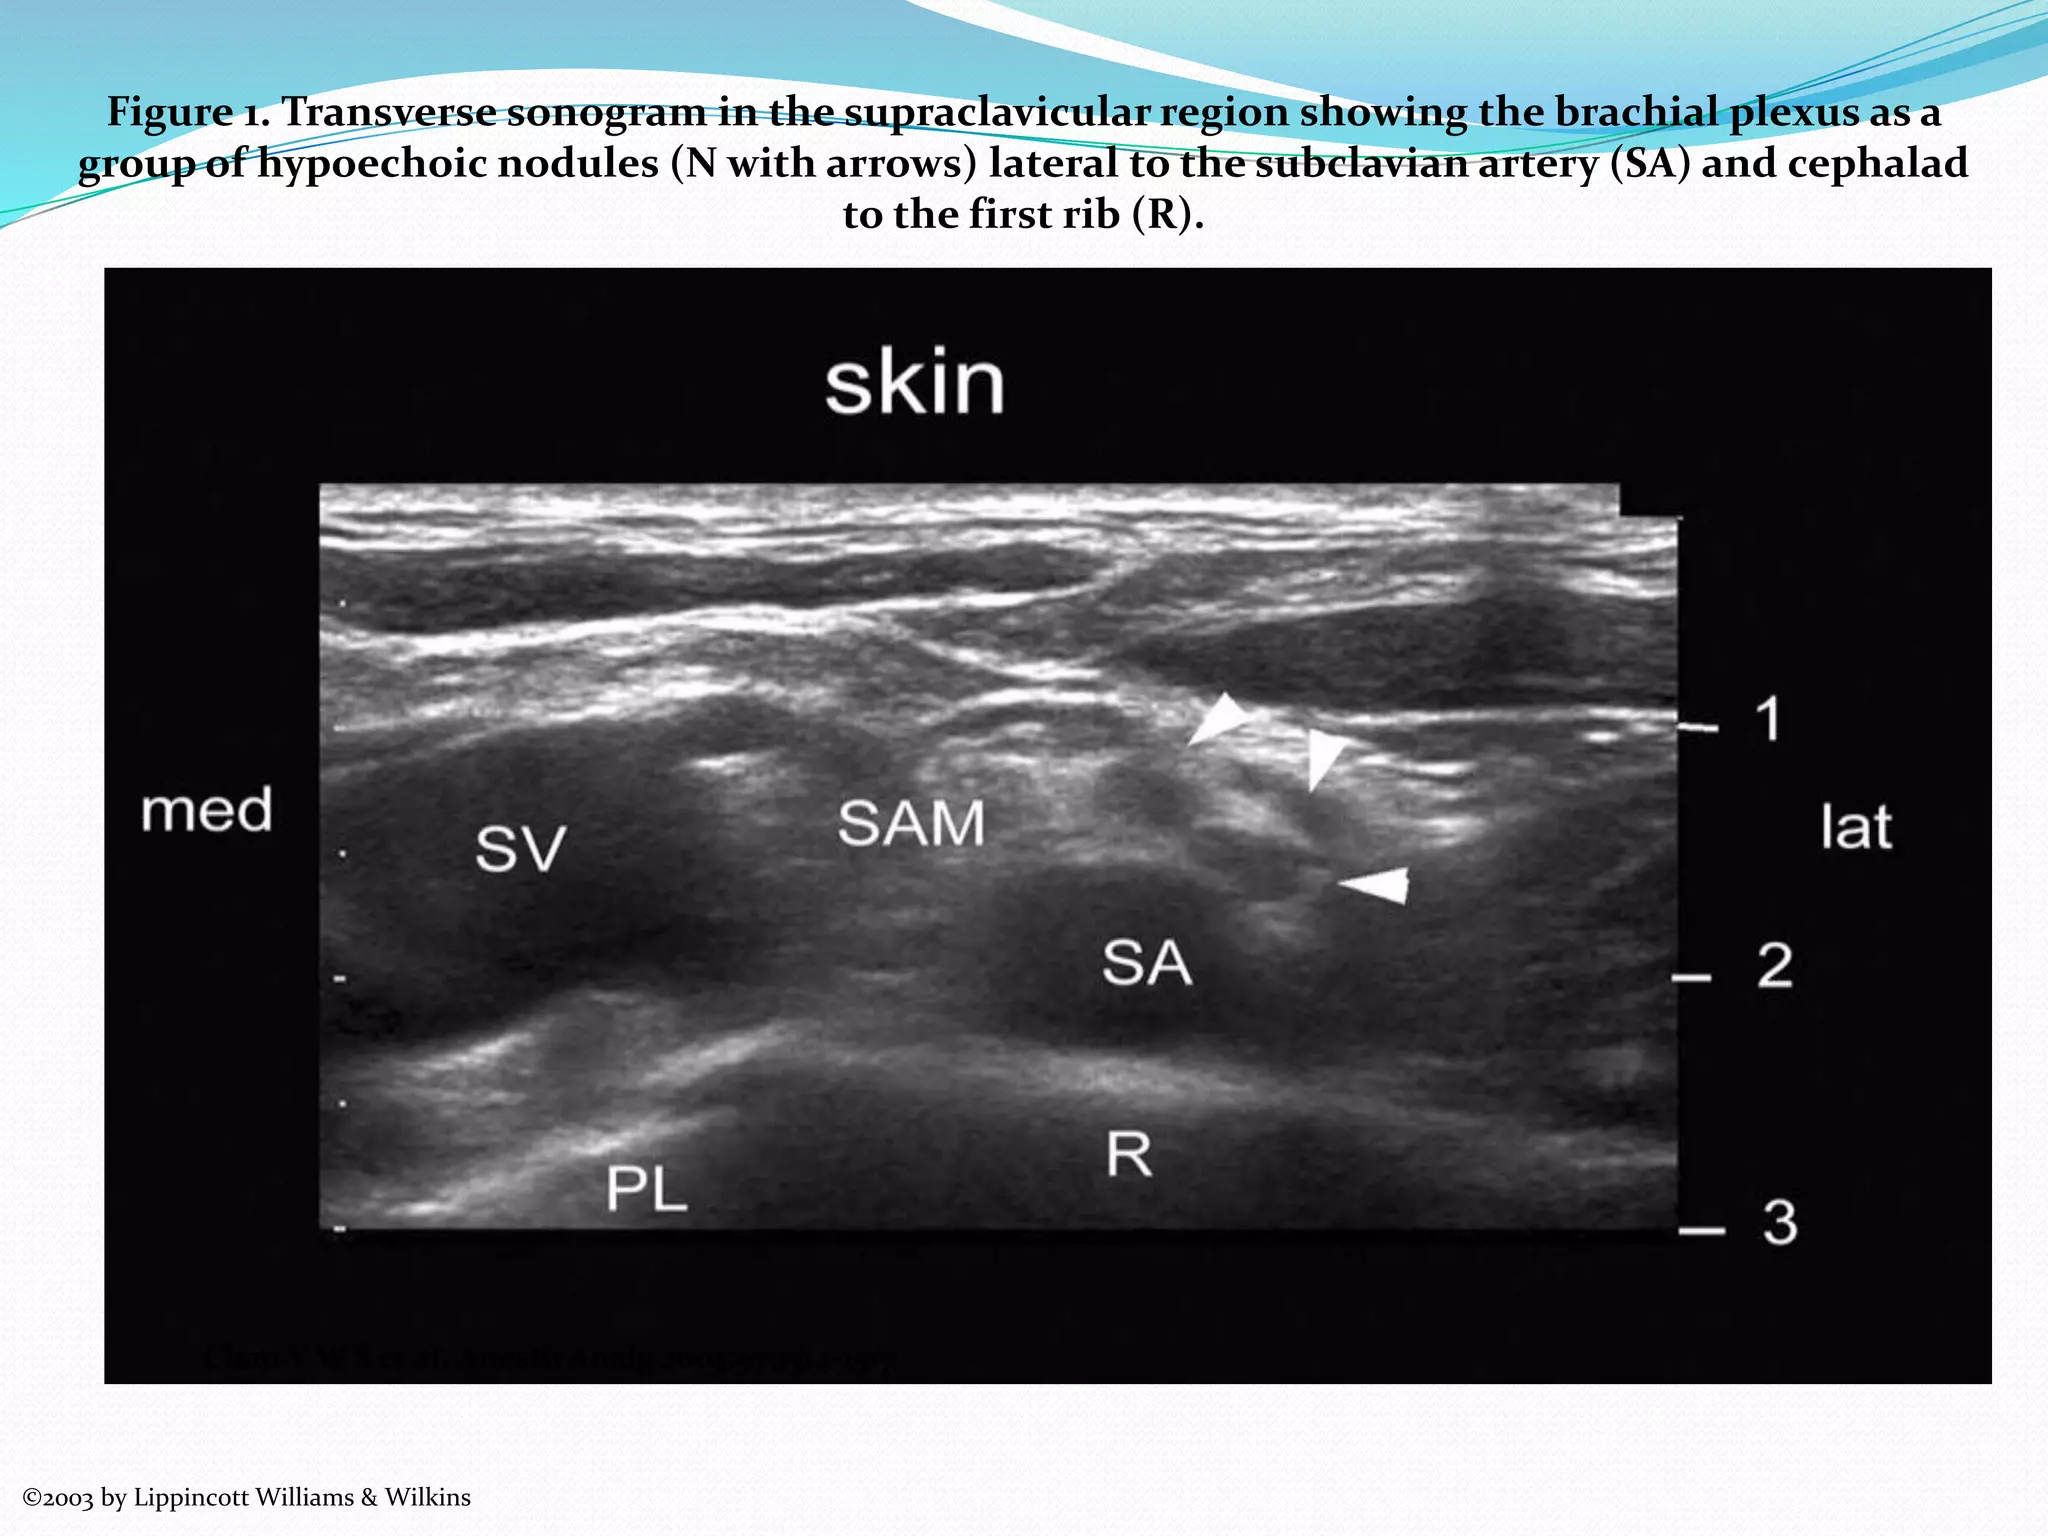

This document provides an overview of brachial plexus anatomy and techniques for brachial plexus nerve blocks. It begins with a description of the brachial plexus formation from cervical and thoracic nerve roots and its branching pattern. Four main approaches for brachial plexus nerve blocks are described: interscalene, supraclavicular, infraclavicular, and axillary. Details are provided on the anatomy and techniques for performing interscalene and supraclavicular brachial plexus blocks. Ultrasound guidance is discussed as an advancement which allows real-time visualization of needle and nerve. Complications are also summarized.